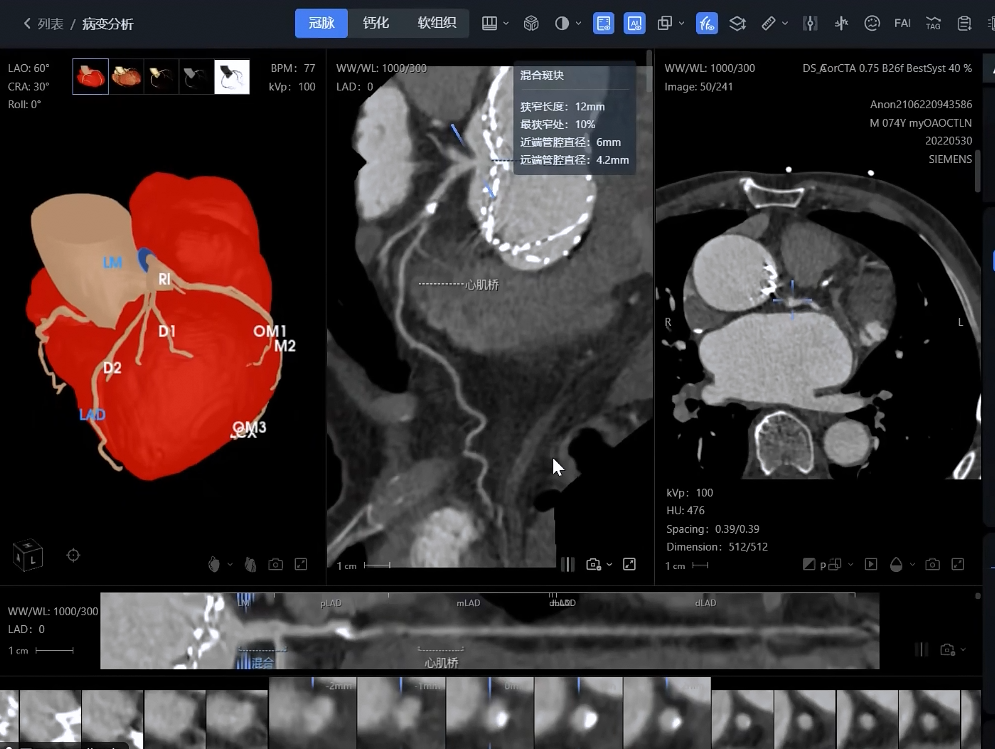

影像智能分析:對(duì)CTA、MRA等多模態(tài)影像進(jìn)行自動(dòng)處理和病變識(shí)別

影像分析方面:系統(tǒng)能夠自動(dòng)處理心血管CTA、腦血管MRA、外周血管超聲等多模態(tài)影像數(shù)據(jù),精準(zhǔn)識(shí)別斑塊性質(zhì)、狹窄程度和病變范圍,生成結(jié)構(gòu)化報(bào)告。